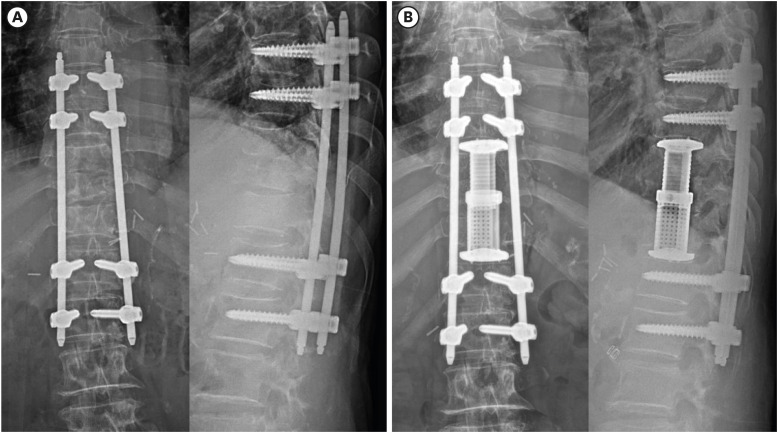

结核性脊柱炎,又称波特病,于1779年由珀西瓦尔·波特首次描述。由于感染的非特异性,结核性脊柱炎的诊断常常被推迟,这可能导致严重的后果。鉴别诊断对化疗后出现淋巴结或骨转移的癌症患者尤为重要。我们提出的情况下,76岁的女性胃癌晚期,谁最初怀疑有转移性脊柱肿瘤和细菌性脊柱炎。患者表现为下肢瘫痪,并被诊断为转移性癌症,导致失去康复的希望。然而,在随后的结核性脊柱炎诊断和多次手术干预后,患者完全缓解并显著改善,最终恢复了独立行走的能力。这个病例强调了准确诊断和及时干预的重要性,在病例的最初表现可能模仿转移性疾病。

Tuberculous (TB) spondylitis, also known as Pott's disease, was first described by Percivall Pott in 1779. The diagnosis of TB spondylitis is often delayed because of the non-specific nature of the infection, which can lead to severe consequences. Differential diagnosis is especially critical in cancer patients undergoing chemotherapy who present with lymph node or bone metastasis. We present the case of a 76-year-old female with advanced gastric cancer, who was initially suspected of having a metastatic spinal tumor and bacterial spondylitis. The patient presented with lower limb paralysis and was diagnosed with metastatic cancer, resulting in a loss of hope for recovery. However, following the subsequent diagnosis of TB spondylitis and multiple surgical interventions, the patient achieved complete remission and significant improvement, ultimately regaining the ability to walk independently. This case highlights the importance of accurate diagnosis and timely intervention in cases where the initial presentations may mimic metastatic disease.